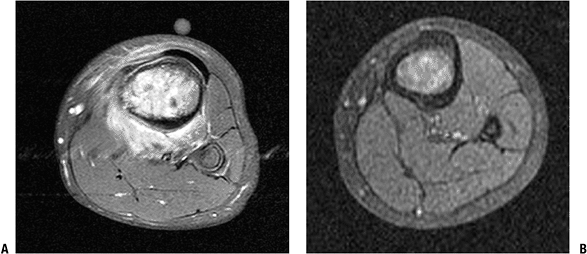

|  |

| Figure 4.3-24 MRI assessment of chemotherapy response. T1-weighted fat-suppressed MR images of an osteogenic sarcoma of the proximal tibia. (A) Considerable edema surrounds the tumor at presentation. (B) The same tumor following 9 weeks of induction chemotherapy. |